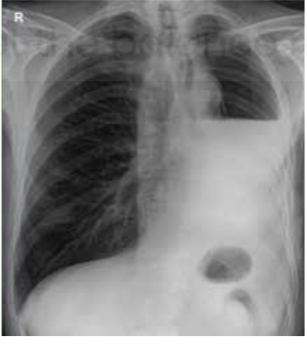

Radiological diagnosis of pleural effusion

Meniscus sign / Ellis S curve